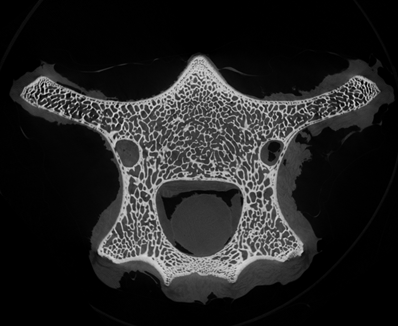

小編很好奇在micro CT掃描中,這些笑臉會是什么樣子?我們選擇了一段羊的脊椎骨放入CT設備中進行掃描,在得到的幾百張切片圖中,挑選出一張“萌萌的大笑臉”。

骨骼CT切片圖